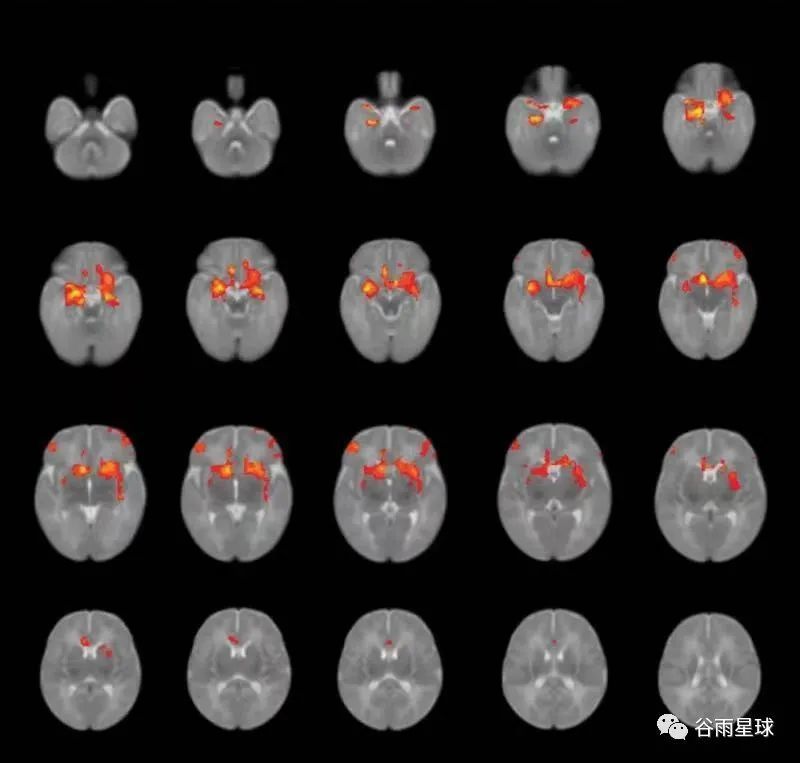

■脑扫描图显示了婴儿杏仁核和其他脑区的连接模式,妈妈在怀孕期间经历的疫情压力会让一些宝宝脑连接变弱。来源:Nature Portfolio